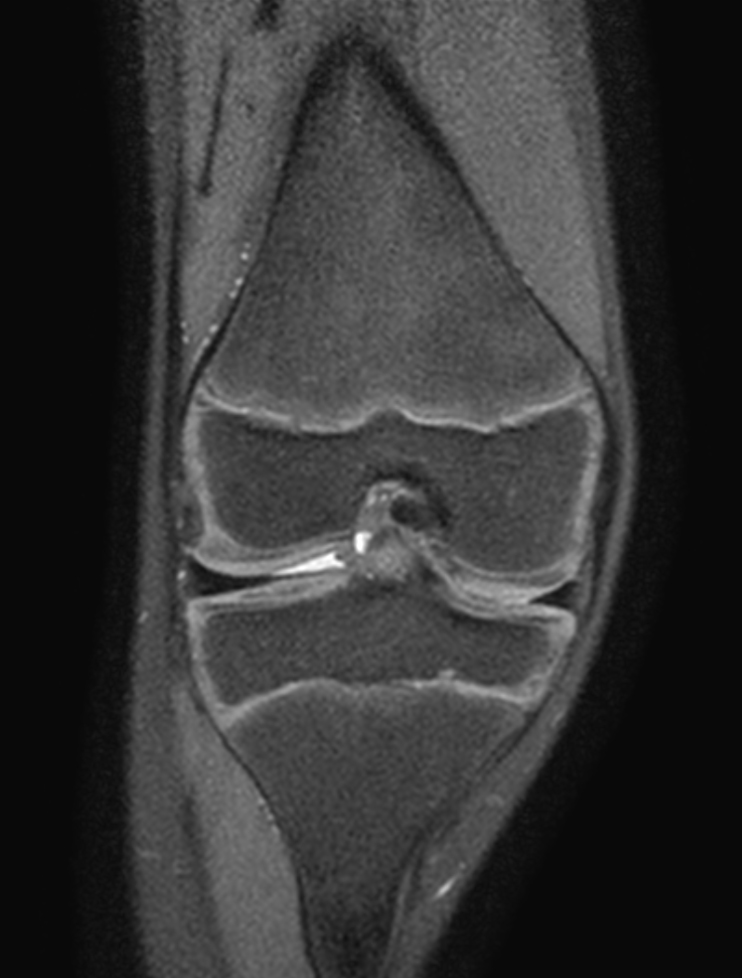

Coronal T1w TSE

Coronal PDw TSE

3D VIEW PDw SPAIR - Coronal reformat